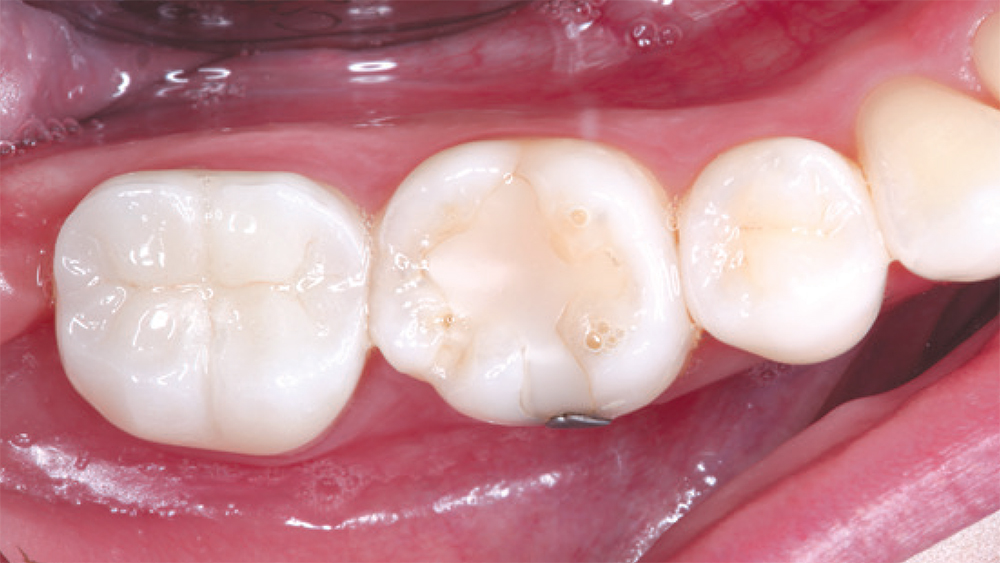

CAMouflage NOW used here to restore teeth #30 and #31, and blended extremely well with the adjacent natural teeth

CAMouflage NOW, which is manufactured in block form for the in-office fabrication of inlays, onlays and full-coverage crowns, was used here to restore teeth #30 and #31, and blended extremely well with the adjacent natural teeth.

– Clinical dentistry by Justin Chi, DDS, CDT